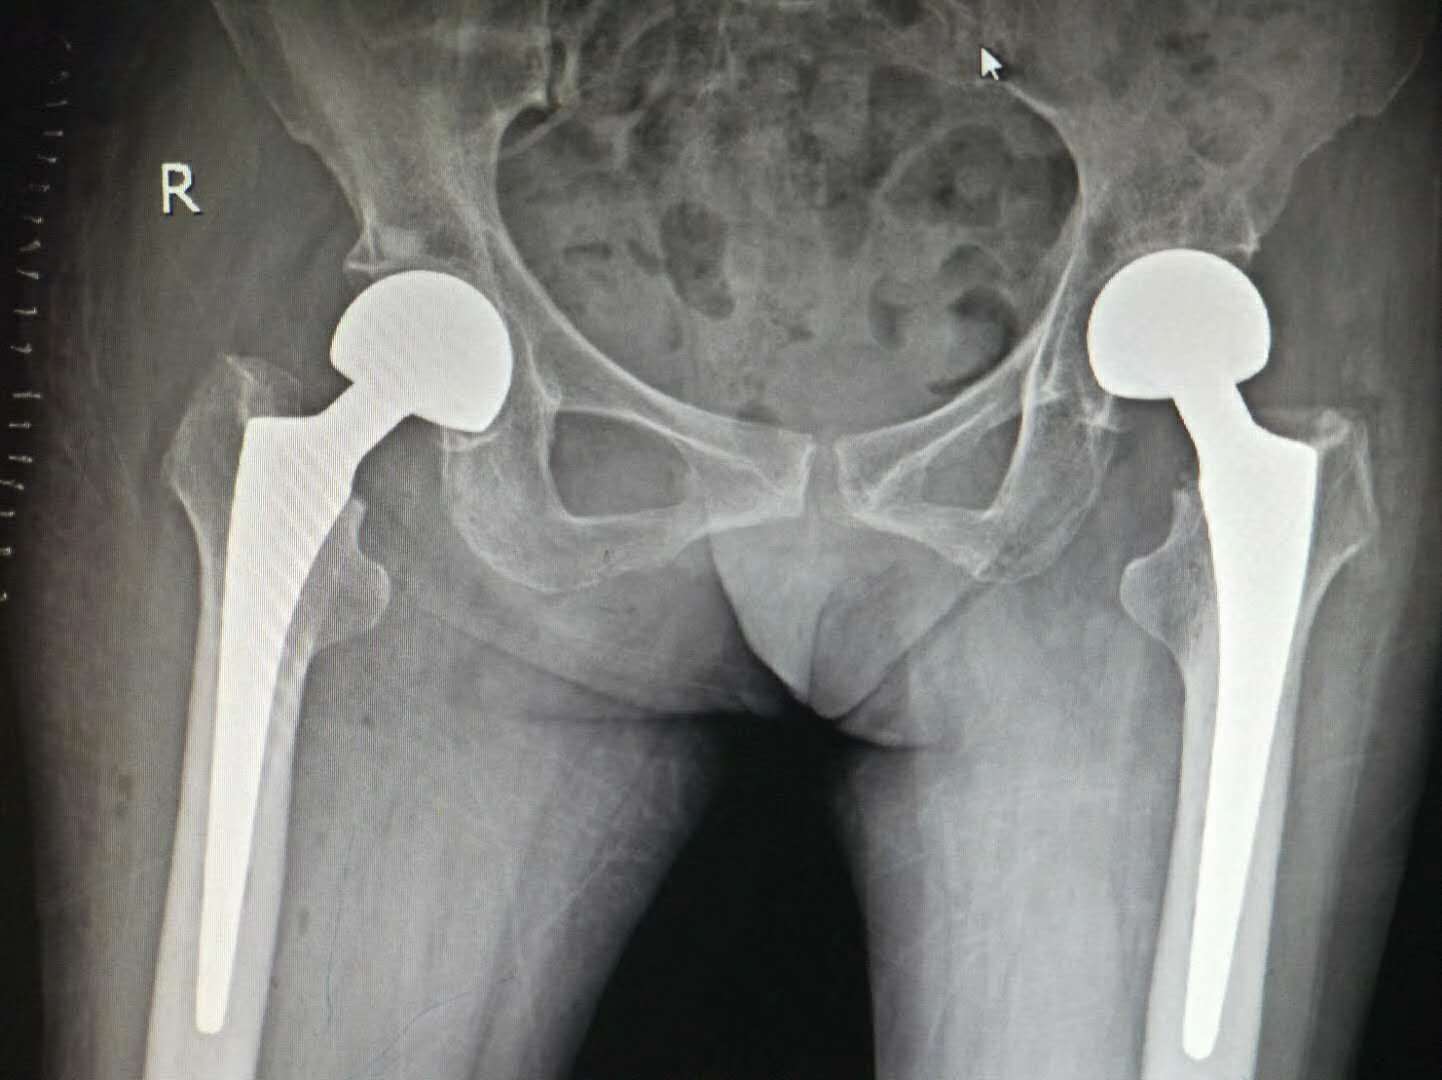

王奶奶这一跤可摔的不轻,她的另一侧的股骨颈又骨折了。面对家属急切的目光,专家们放弃与家人团聚的时间,对王奶奶病情及身体状况进行分析探讨。对于这位特殊的病人,专家们讨论后,综合考虑认为“手术治疗是最佳的治疗方案”。有了上次手术成功带来的喜悦,为提高王奶奶晚年生活质量,家属同意再次手术治疗。因王奶奶为高龄骨折患者,已施行过左股骨颈骨折人工半髋关节置换术,又有冠心病,院方决定再次为王奶奶进行人工髋关节置换术,并制定了详细治疗方案及应急预案。经过前期治疗和调理,2月22日在多科室通力合作下医院为其实施右股骨颈骨折人工半髋关节置换术。麻醉、消毒、切开髋关节部位、切除股骨头、置入股骨头假体、复位人工髋关节、止血、固定、缝合,一系列动作娴熟、规范。整个手术时间约40分钟、出血量少,王奶奶再次成功“换骨”。术后的第三天,王奶奶已经可以拄拐下地行走了!

随着社会人口老龄化的加剧,高龄骨折患者的比例逐年上升,股骨骨折已成为老年人跌倒后常见损伤。据关节科主任、刘文志副主任医生介绍“对于高龄股骨骨折患者,采用人工关节置换术,可以使患者早日下床,减少因传统观念卧床而引起的并发症,降低死亡率,减低患者痛苦,减轻患者家属负担,明显改善患者生活质量,让其重拾生活信心,重享幸福晚年。” 娄底市骨伤医院每年收治大量的高龄骨折患者,人工髋、膝关节置换术取得了优良的治疗效果,获得广大患者及家属信任,许多外地患者慕名前来。